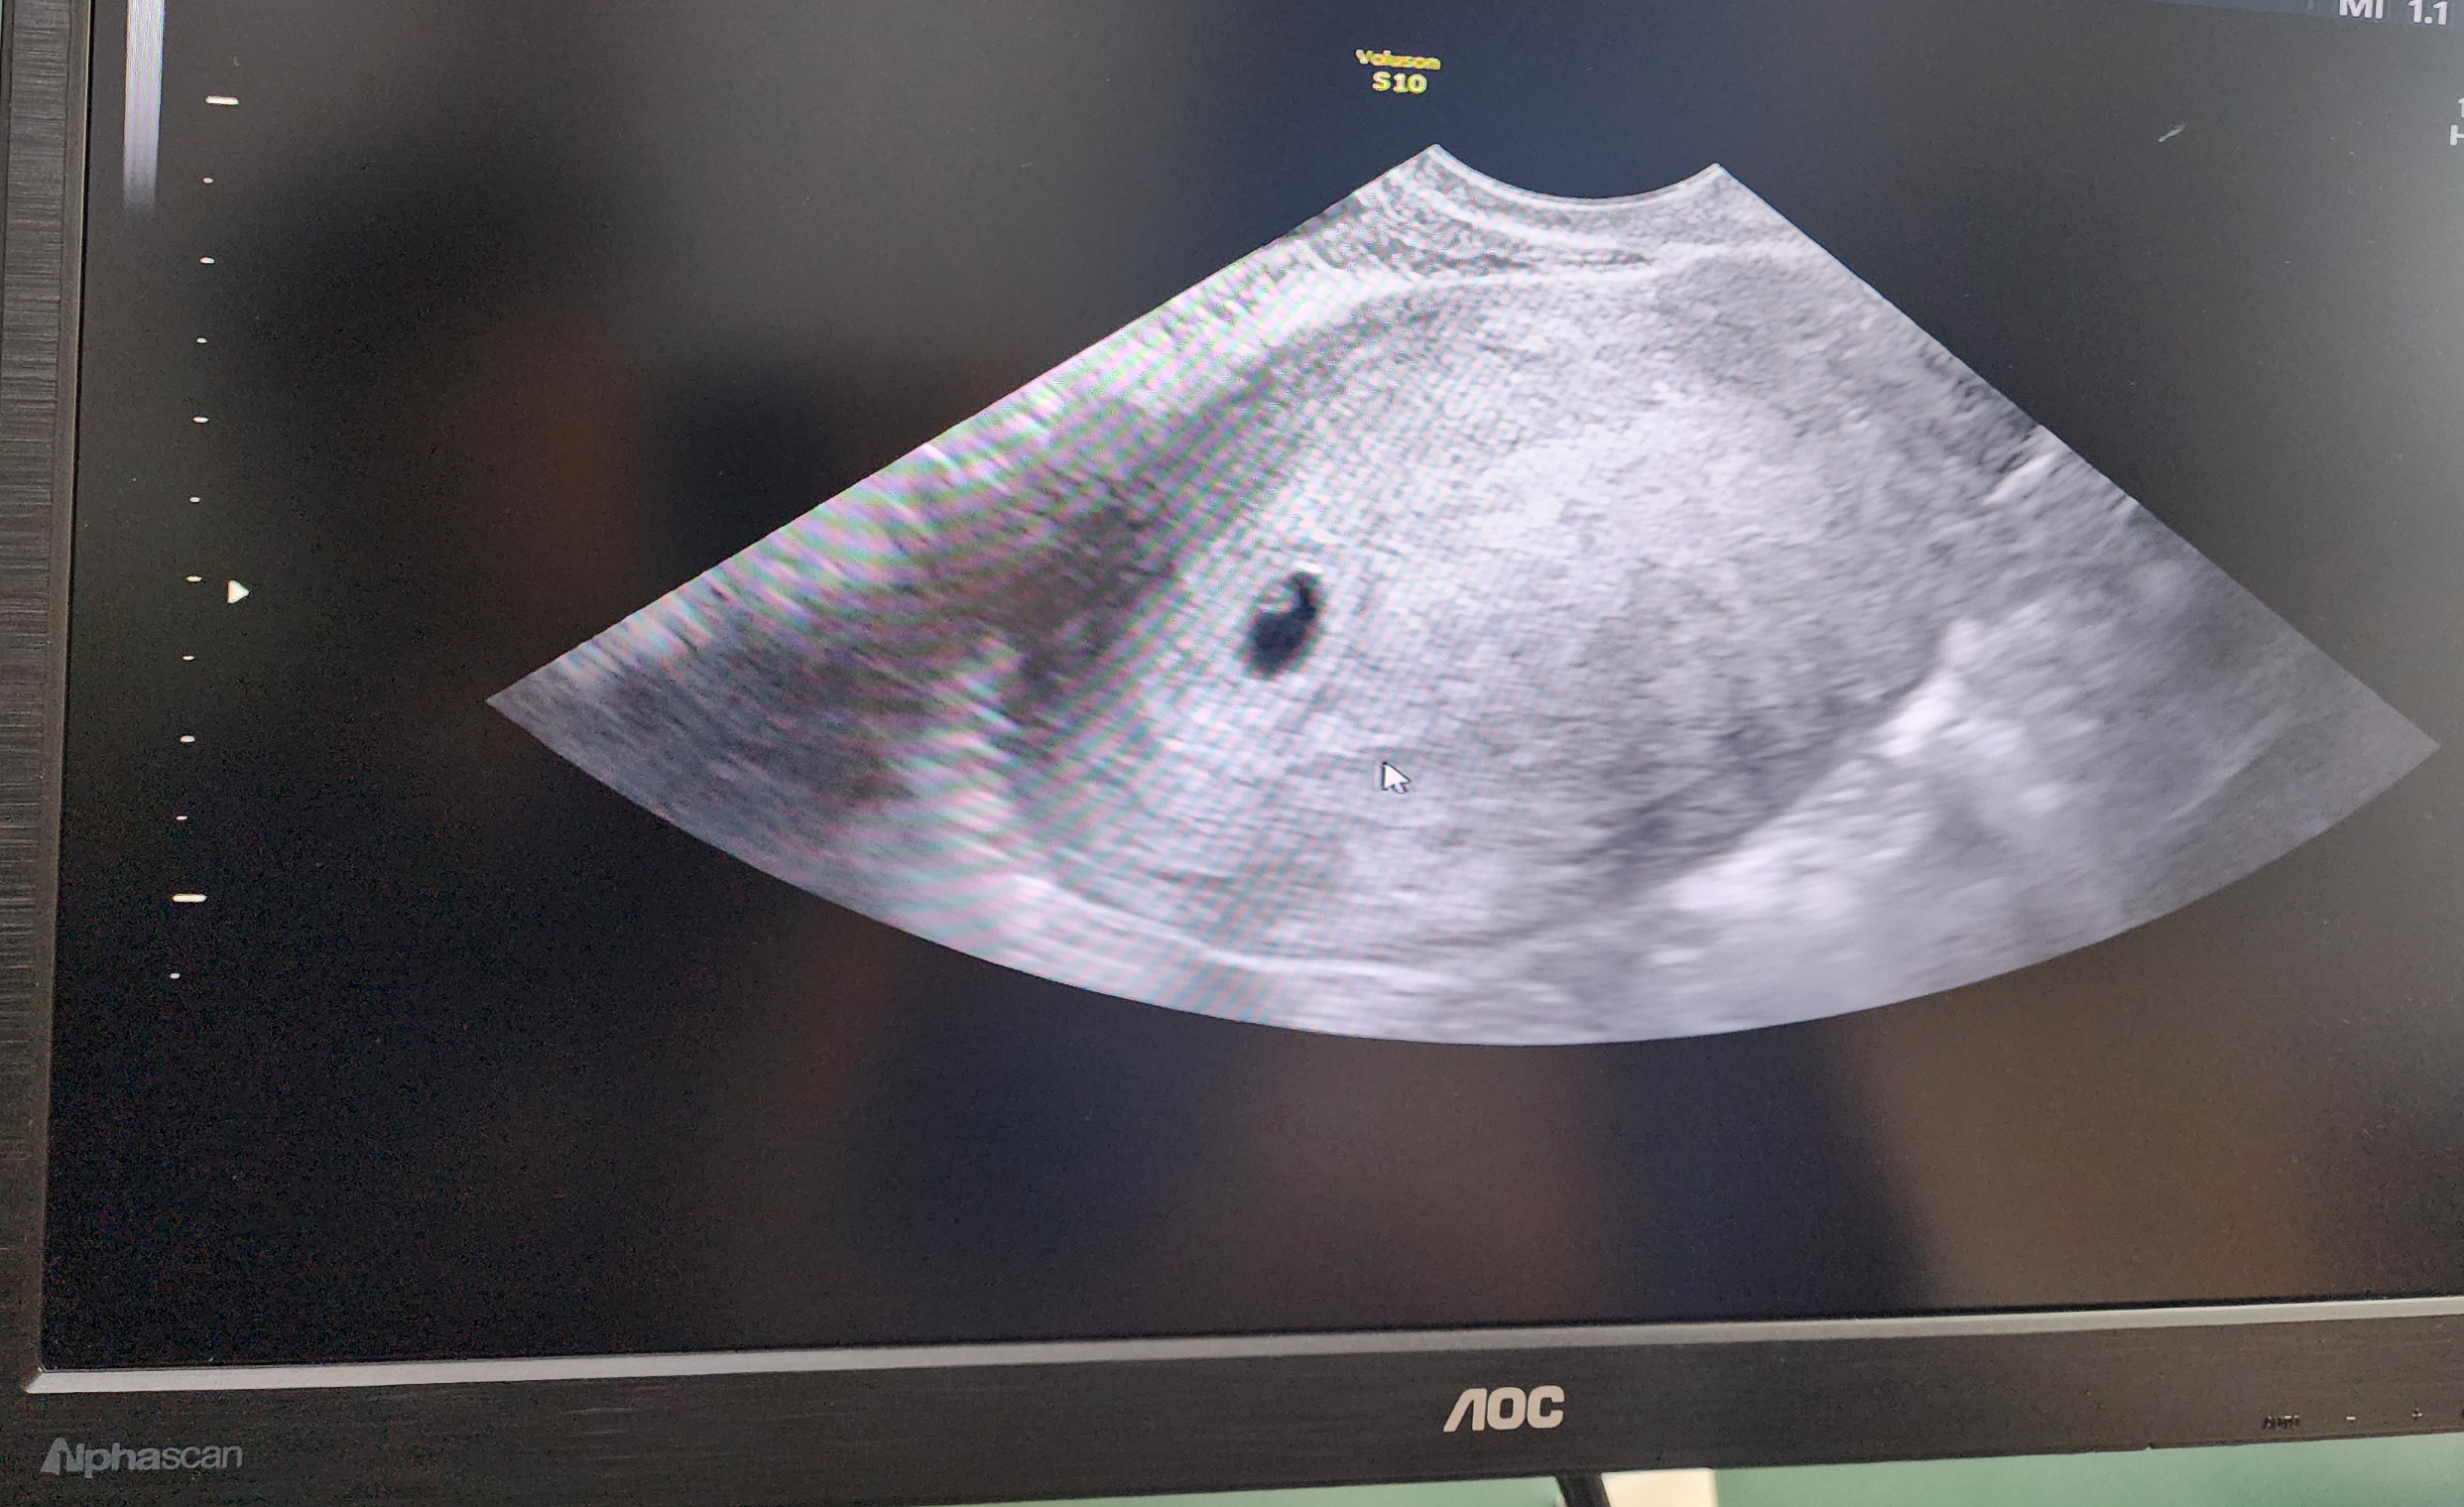

애기집

임신 4~5주차입니다. 애기집과 난황이 발견되었어요.

아직은 작디 작은 존재이지만, 앞으로 건강하게 자라기를 바래봅니다.